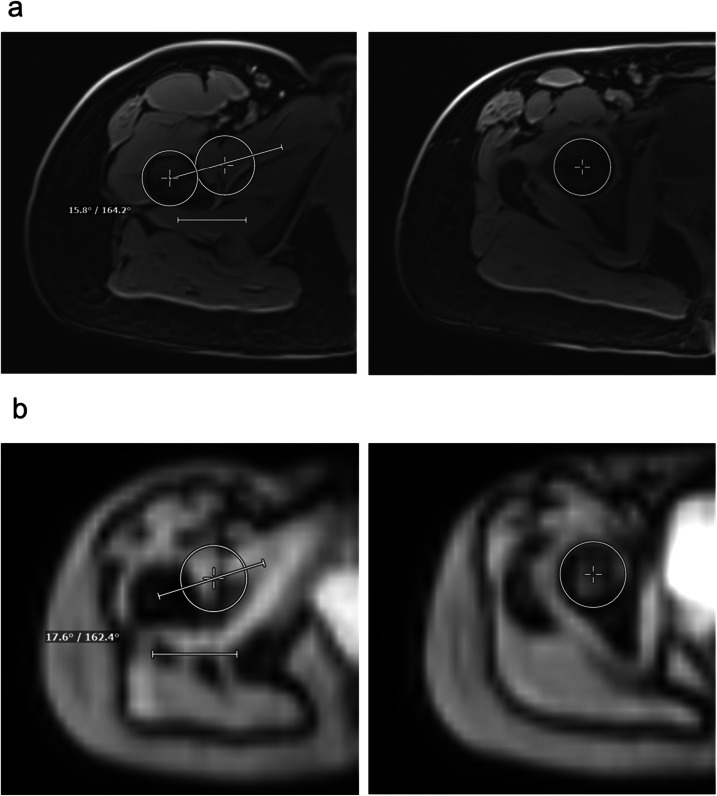

Computed tomography (CT) and magnetic resonance imaging (MRI) are commonly used to assess femoral and tibial torsion. While CT offers high spatial resolution, it involves ionizing radiation. MRI avoids radiation but requires multiple sequences and extended acquisition time. We retrospectively evaluated whether a three-dimensional isotropic MRI localizer (FastView) could serve as a reliable and faster alternative. In this retrospective single-center study, 60 lower limbs from 30 patients, aged 27.1 ± 11.5 years (mean ± standard deviation), 19 females and 11 males, were assessed using both FastView and a dedicated MRI protocol. FastView (5 × 5 × 5 mm3 voxels) imaged the entire lower limb in 17.4 s compared to nearly 7 min for the dedicated protocol. Torsion angles were measured independently by two readers. Agreement between methods was evaluated using intraclass correlation coefficients (ICCs), Bland-Altman plots, and Pearson R². No significant differences in torsion values were found (all p > 0.305). Femoral (ICC: 0.91-0.96) and tibial (ICC: 0.91-0.94) torsion showed excellent inter-modality agreement. Inter-reader reliability was also high (ICC: 0.95-0.99). Correlation values confirmed strong agreement (R²: 0.891-0.963). FastView demonstrated accuracy comparable to the dedicated protocol, offering a fast, efficient, and radiation-free option for routine torsion assessment. RELEVANCE STATEMENT: FastView MRI localizer offers a fast and resource-efficient method for assessing lower limb torsion, potentially replacing standard multisequence protocols in routine clinical practice. KEY POINTS: FastView MRI enables lower limb torsion measurements with full-limb coverage in under 20 s. Torsion angles from FastView and dedicated MRI showed no significant differences. Femoral and tibial ICCs between 0.91 and 0.96 confirm excellent inter-protocol agreement. Inter-reader agreement was consistently high across both protocols. FastView may replace multisequence MRI protocols in routine clinical torsion assessment.